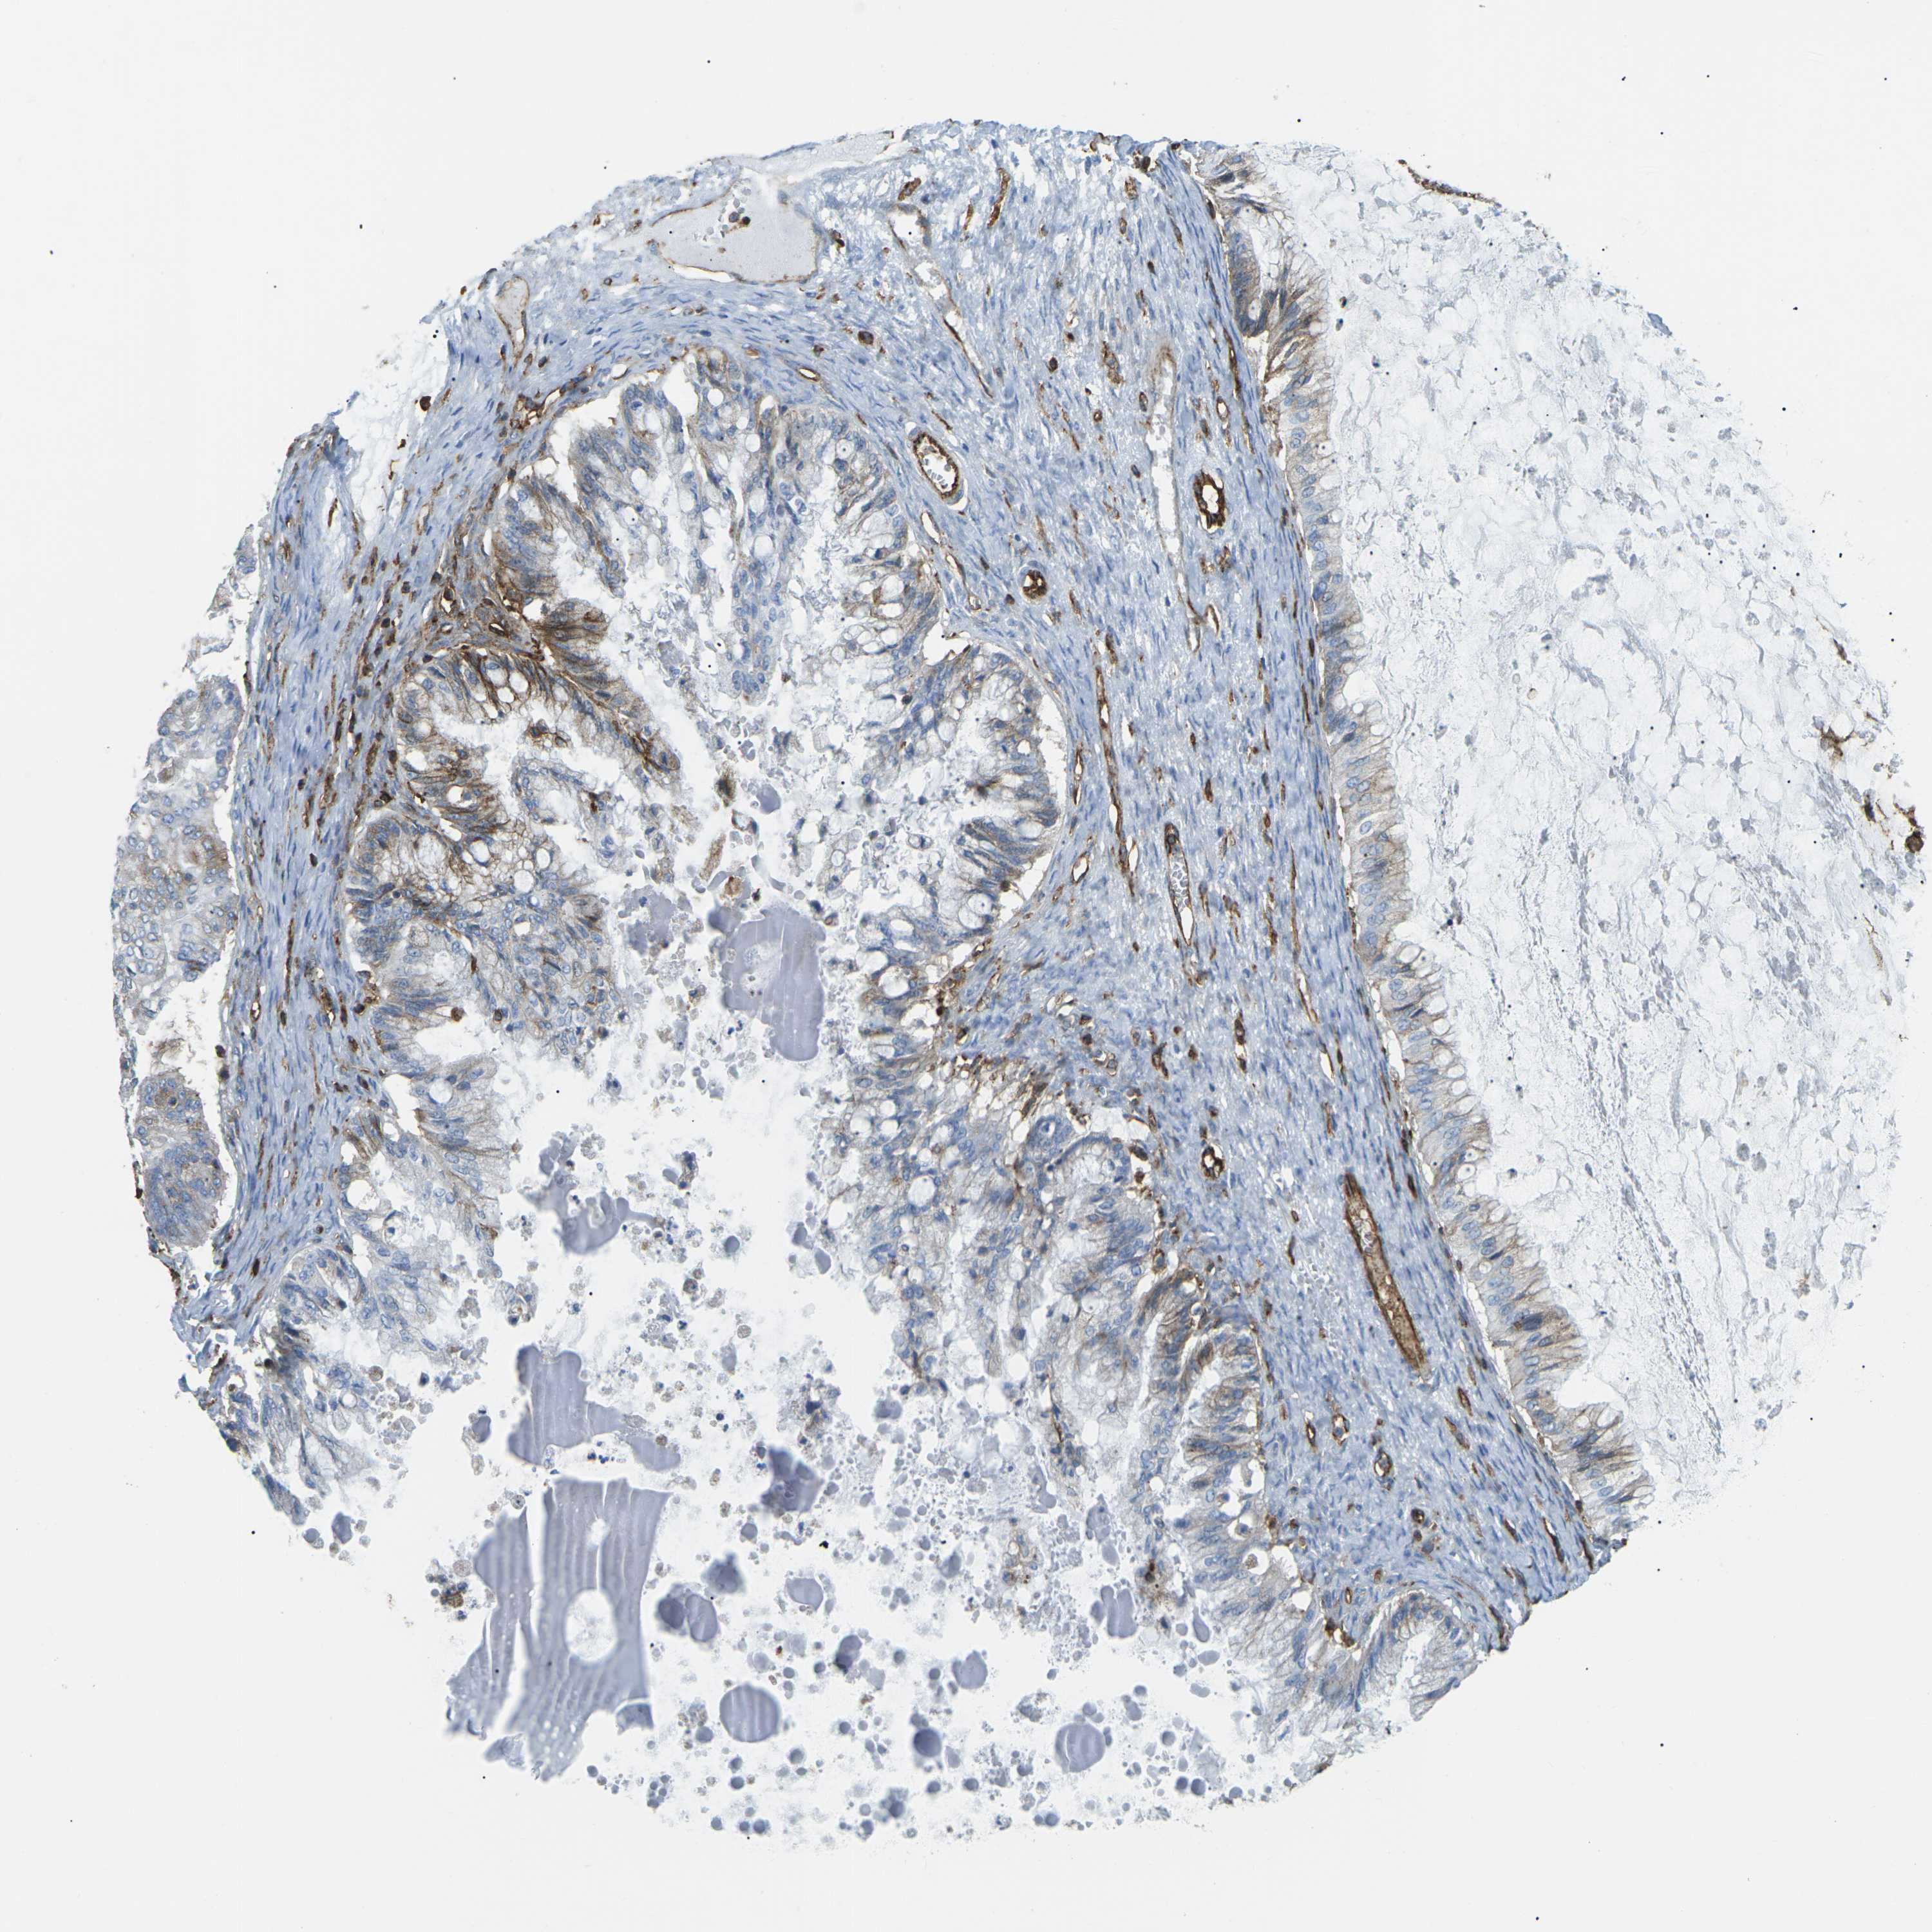

OVARIAN CANCER - Protein expressioni

A mouse-over function shows sample information and annotation data. Click on an image to view it in a full screen mode. Samples can be filtered based on level of antibody staining by selecting one or several of the following categories: high, medium, low and not detected. The assay and annotation is described here.

Note that samples used for immunohistochemistry by the Human Protein Atlas do not correspond to samples in the TCGA dataset.

Antibody stainingi

Antibody staining in the annotated cell types in the current human tissue is reported as not detected, low, medium, or high, based on conventional immunohistochemistry profiling in selected tissues. This score is based on the combination of the staining intensity and fraction of stained cells.

Each image is clickable and will lead to virtual microscopy that enables deeper exploration of all samples and also displays staining intensity scores, fraction scores and subcellular localization as well as patient and tissue information for each sample.

Antibody CAB015418

Staining

High

Medium

Low

Not detected

Intensity

Strong

Moderate

Weak

Negative

Quantity

>75%

75%-25%

<25%

None

Location

Nuclear

Cytoplasmic/membranous

Cytoplasmic/membranous,nuclear

Cystadenocarcinoma, serous, NOS

Carcinoma, endometroid

Cystadenocarcinoma, mucinous, NOS

Carcinoma, NOS